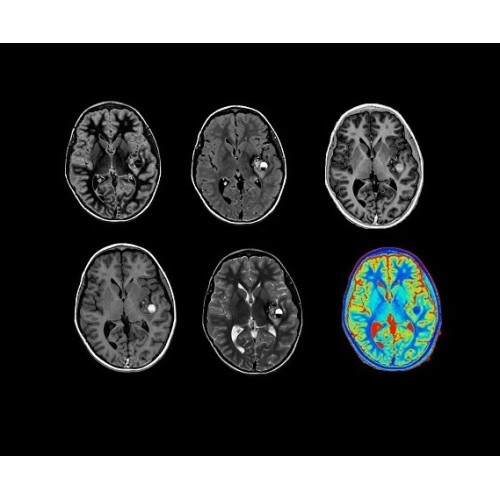

Компания GE Healthcare представляет революционную, полностью интегрированную систему SIGNA PET/MR1, в которой сочетаются времяпролетная технология (TOF) и возможности напряженности магнитного поля 3.0 Тл. Мы поможем вам поднять исследования на более высокий уровень. SIGNA PET/MR позволяет достичь впечатляющей точности и скорости исследований, а благодаря новейшей технологии реконструкции Q.Clear2 качество изображений улучшается в два раза. Кроме того, в систему включен полный набор клинических приложений и гибких катушек для проведения любых видов исследования, открывая для вас возможности визуализации, о которых вы даже не догадывались.

• TurboTOF — инновационная технология позволяет корректировать коэффициент затухания сигнала и минимизировать потери анатомических данных, создавая МР-систему для количественной визуализации.

• Q.Clear — в основу технологии легли накопленные знания о том, как минимизировать помехи при реконструкции и получить четкое изображение. При значительном улучшении качества изображения сохраняется точность расчетов. Сочетание технологии TOF и реконструкции Q.Clear — ваш надежный помощник для получения точных и достоверных данных.

• Специальный пакет приложений для измерения и сравнения объемных изображений ЦНС с нормами поможет вам в диагностике нейродегенеративных заболеваний, а дополнительные инструменты визуализации — в постановке точного диагноза с помощью бета-амилоидов и радиоизотопных маркеров ФДГ.